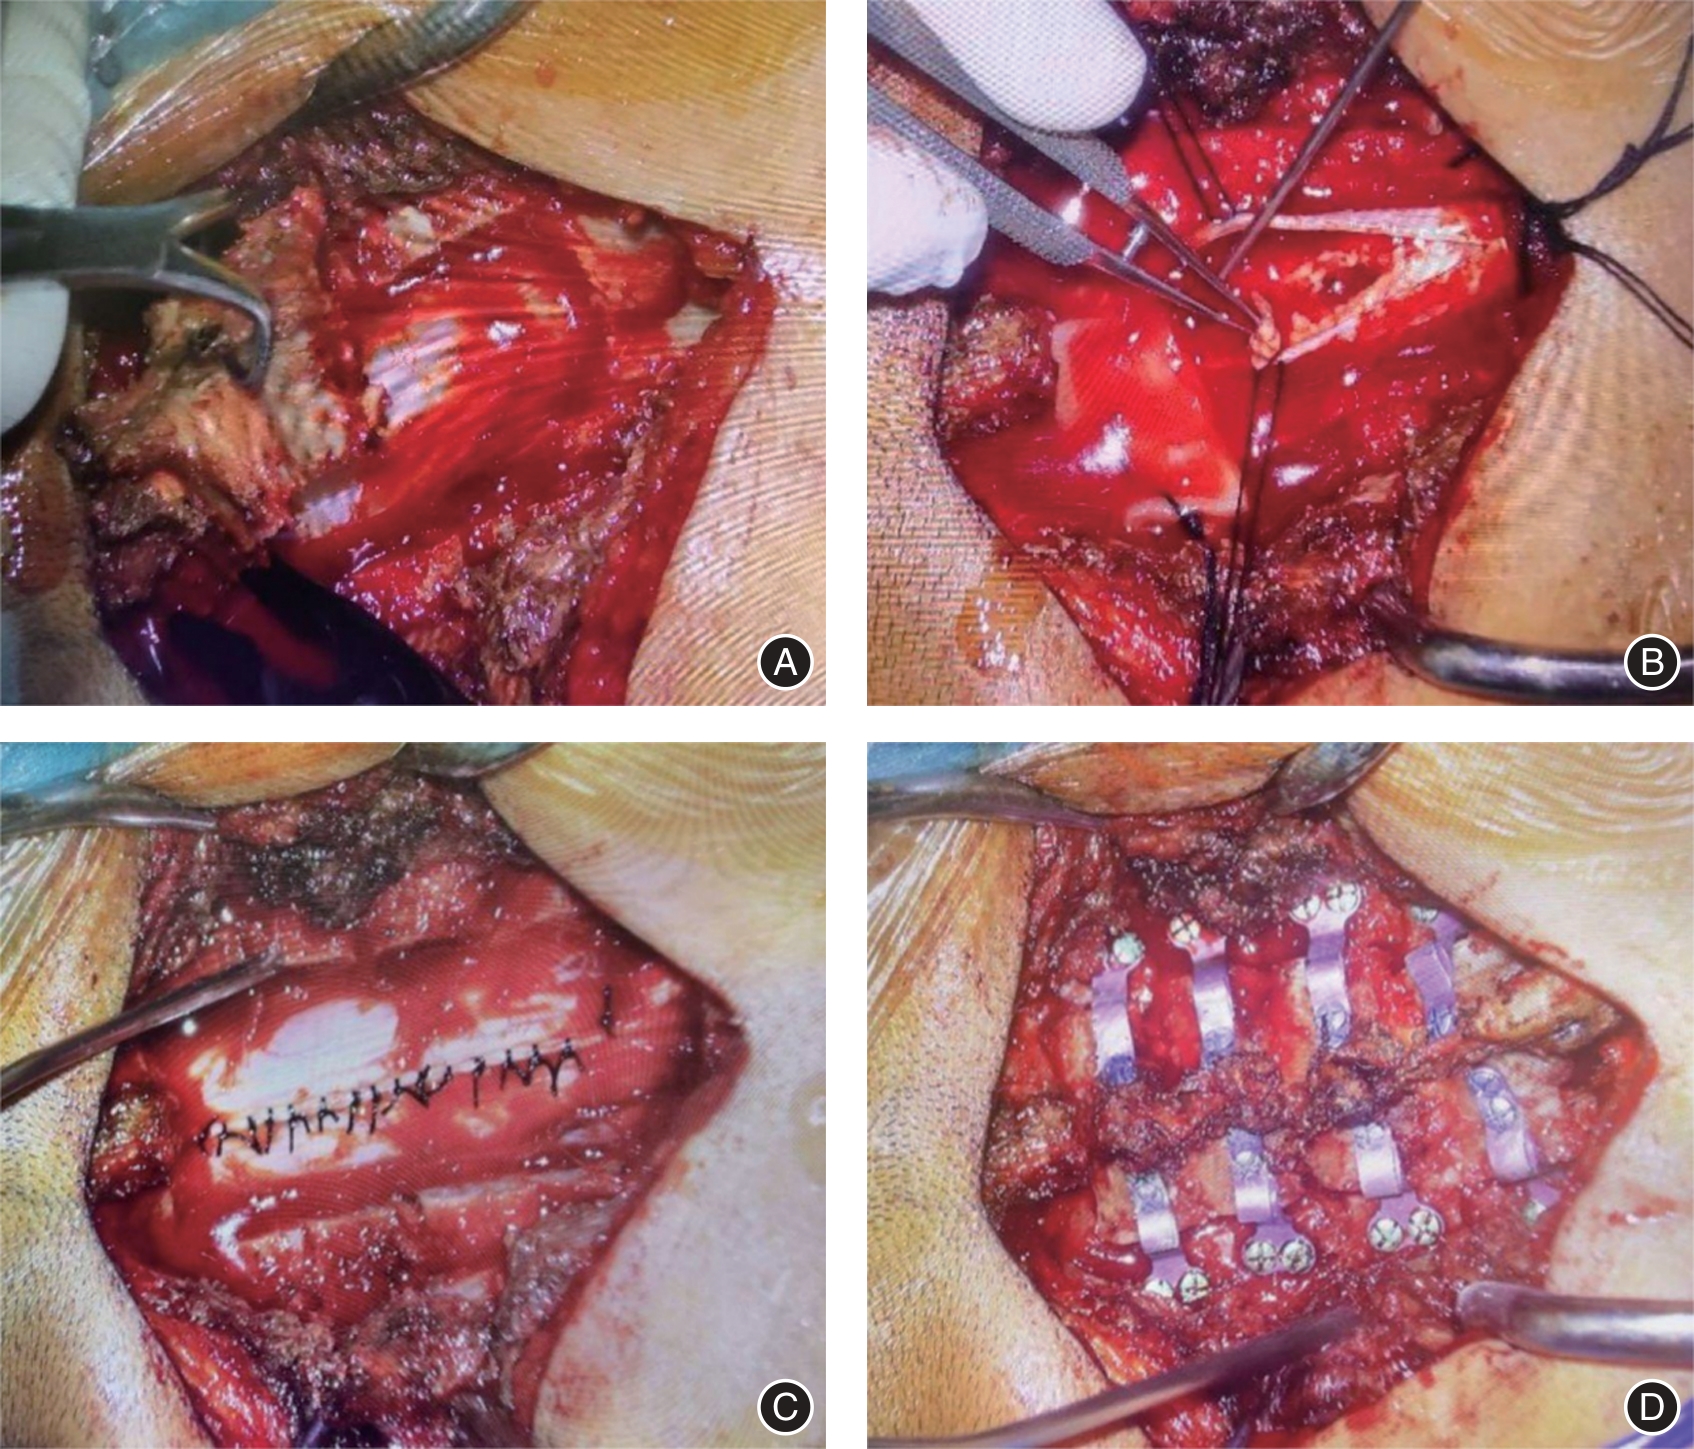

目的 研究用于辅助椎管内肿瘤切除手术的3D显微镜技术对椎管内肿瘤疾病的临床治疗效果与安全性。 方法 分析2019年1月至2023年7月治疗的椎管内肿瘤患者37例,采用3D显微镜下肿瘤切除(3D组)治疗的患者15例,采用普通显微镜下肿瘤切除(普通组)治疗的患者22例。比较两组患者的围术期指标、临床疗效指标、安全性指标。 结果 普通组手术时间(223.78 ± 46.46)min,3D组手术时间(182.93 ± 39.28)min,与普通组相比手术时间明显偏低(P < 0.05),其他围手术期指标两组比较差异无统计学意义(P > 0.05)。所有患者在术后疼痛症状均得到明显减轻,并且在一定程度上恢复了较好神经功能。对比术前,两组患者术后24 h以及术后1年的VAS评分,差异有统计学意义(P < 0.01),组间比较差异无统计学意义(P > 0.05), McCormick脊髓功能评级在术后1年均为Ⅰ级。两组术后并发症发生率差异无统计学意义。 结论 使用3D显微镜技术与普通显微镜技术进行椎管内肿瘤手术均具有较好的临床疗效。但于3D显微镜下能明显缩短手术时间,以此降低手术并发症的风险,具有更优的临床安全性。

Objective To investigate the clinical treatment effect and safety of 3D microscopy technology for adjuvant neuraxial tumor resection on neuraxial tumor diseases. Methods A total of 37 patients with neuraxial tumors treated from January 2019 to July 2023, 15 patients treated with 3D microscope tumor resection (3D group), and 22 patients treated with general microscope tumor resection (ordinary group) were analyzed. The perioperative indexes, clinical efficacy indexes and safety indexes were compared between the two groups. Results The operation time was (223.78 ± 46.46) min in the ordinary group and (182.93 ± 39.28) min in the 3D group, which was significantly lower than that in the ordinary group (P < 0.05), and there was no significant difference in other perioperative indicators between the two groups (P > 0.05). All patients had significantly reduced their postoperative pain symptoms and recovered their neurological function to a certain extent. There were statistically significant differences between the two groups (P < 0.01), but there was no statistical difference between the two groups (P > 0.05), and the McCormick spinal cord function rating was grade I. at one year after surgery. Conclusion The use of 3D microscopy and general microscopy for neuraxial tumor surgery has good clinical efficacy. However, the operation time can be significantly shortened under 3D microscopy, thereby reducing the risk of surgical complications and has better clinical safety.